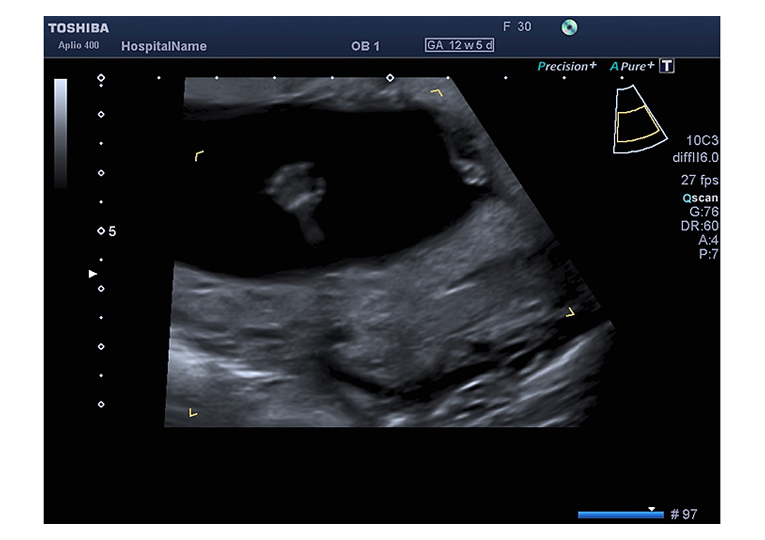

Schon sehr früh in der Schwangerschaft (zwischen 11+0 und 13+6 Schwangerschaftswoche) kann mittels hochauflösender Ultraschallgeräte eine detaillierte Untersuchung Ihres Kindes erfolgen.

Bei dieser Nackentransparenz handelt es sich um eine Flüssigkeitsansammlung im Nacken des Feten, welche bei jedem Kind mehr oder weniger in dieser Phase der Schwangerschaft auftritt. Je nach Grösse des Kindes sind 0,8 bis 2,5 mm „Nackentransparenz“ normal. Eine Verbreiterung dieser „Nackentransparenz“ kann ein Hinweis auf eine Chromosomenstörung, einen Herzfehler oder eine andere Erkrankung des Feten sein. Jedoch können auch gesunde Kinder eine verbreiterte Nackentransparenz aufweisen. Es sind oft nur wenige zehntel Millimeter, um welche die Nackentransparenz bei einem „auffälligen“ Kind vergrößert ist. Daher ist für die Messung ein gutes Ultraschallgerät, Erfahrung und eine spezielle Ausbildung nötig. Generell gilt jedoch: Je breiter die Nackentransparenz, je größer die Wahrscheinlichkeit für ein genetisch oder organisch erkranktes Kind.